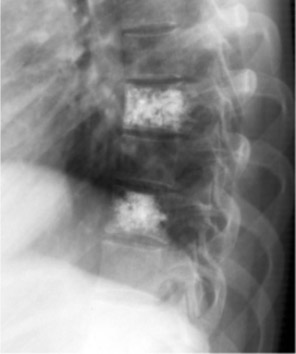

Рис.№4. Рентгенограмма грудного отдела позвоночника в боковой проекции. Определяется удовлетворительное положение костного цемента в телах Th7 и Th9 позвонков.

Рис. №5. Рентгенограмма грудного отдела позвоночника в прямой проекции. Определяется удовлетворительное положение костного цемента в телах Th7 и Th9 позвонков.